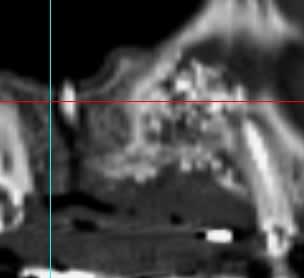

D'aprés ce que je vois, il semblerait qu'il n'y ait pas eu de greffe d'apposition à proprement parlé, mais utilisation d'une portion de corticale en occlusal pour maintenir le bio-oss.

Si ce que je vois à gauche est une vis, elle s'est mobilisée et tout le reste avec.

Il semblerait qu'il y ait eu , de plus, colonisation de la greffe d'une part via la vis qui transperce le sinus, et d'autres part part la dent adjacente ( image radio claire autour de cette dent).

Personnellement je pense que la greffe n'a pas fonctionnée et que ton confrère va se retrouver dans une bouillie inutilisable.